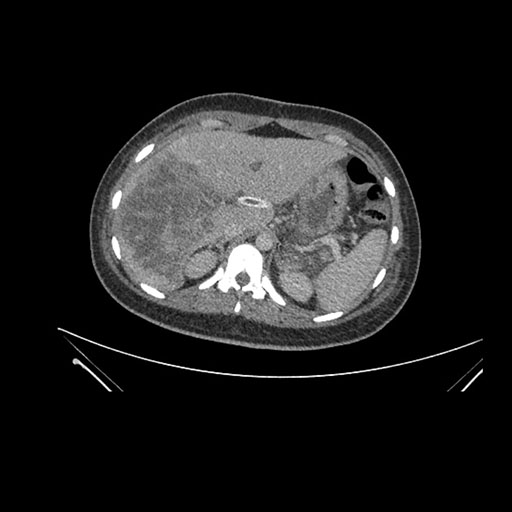

Imaging Analysis

Look through the patient's CT scan to identify any areas of concern for the necessary procedure.

Axial Arterial

Based on initial findings, which issue(s) would you be most concerned about?